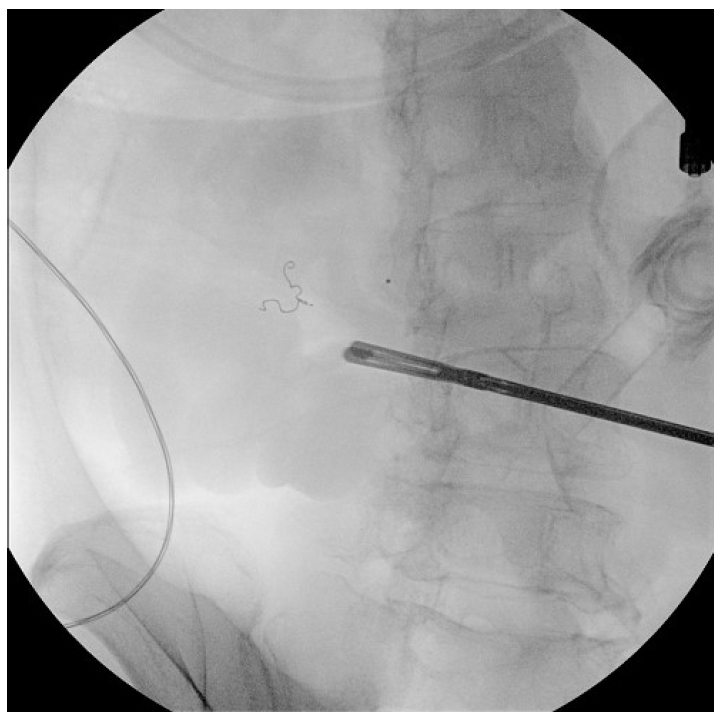

다음날 오후 추가로 혈변이 있어 다시 수혈 후 복부 출혈 CT와 혈관조영술을 재시행하였다. 이 검사에서 이전 코일 색전술이 시행된 부위의 원위부에서 동맥궁(arterial arcades)을 통한 측부 혈관 흐름(collateral flow)으로 인한 것으로 보이는 혈관 외 유출이 관찰되었다(Fig. 3). 원위 회장동맥에 색전술을 수차례 시도하였으나 근위부 동맥에 색전술 시행 시 소장 괴사 가능성이 있어 중단하였고 이후 경과 관찰 중 혈압이 70/50 mmHg까지 떨어지는 등 지속적인 장출혈이 의심되어 수술적 절제를 진행하였다.

Figure 3.

Despite the in situ coil within the superior mesenteric artery, collateral blood flow to the distal branch resulted in rebleeding (red arrow).